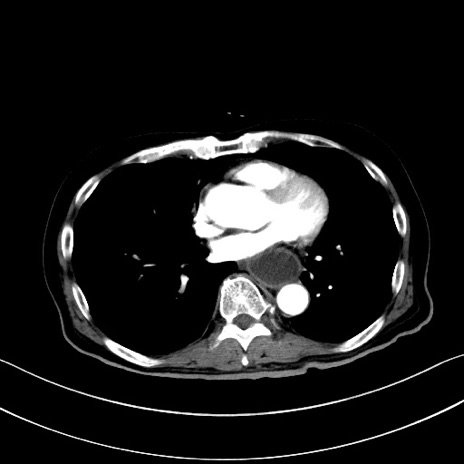

冠状断像

【症例】60歳代男性

【主訴】嘔吐

【現病歴】胃癌にて胃全摘後。食思不振が悪化し、夜中に嘔吐することがある。

【既往歴】胃癌、胃全摘、脾摘、胆摘後

【データ】WBC 5900、CRP 10.56